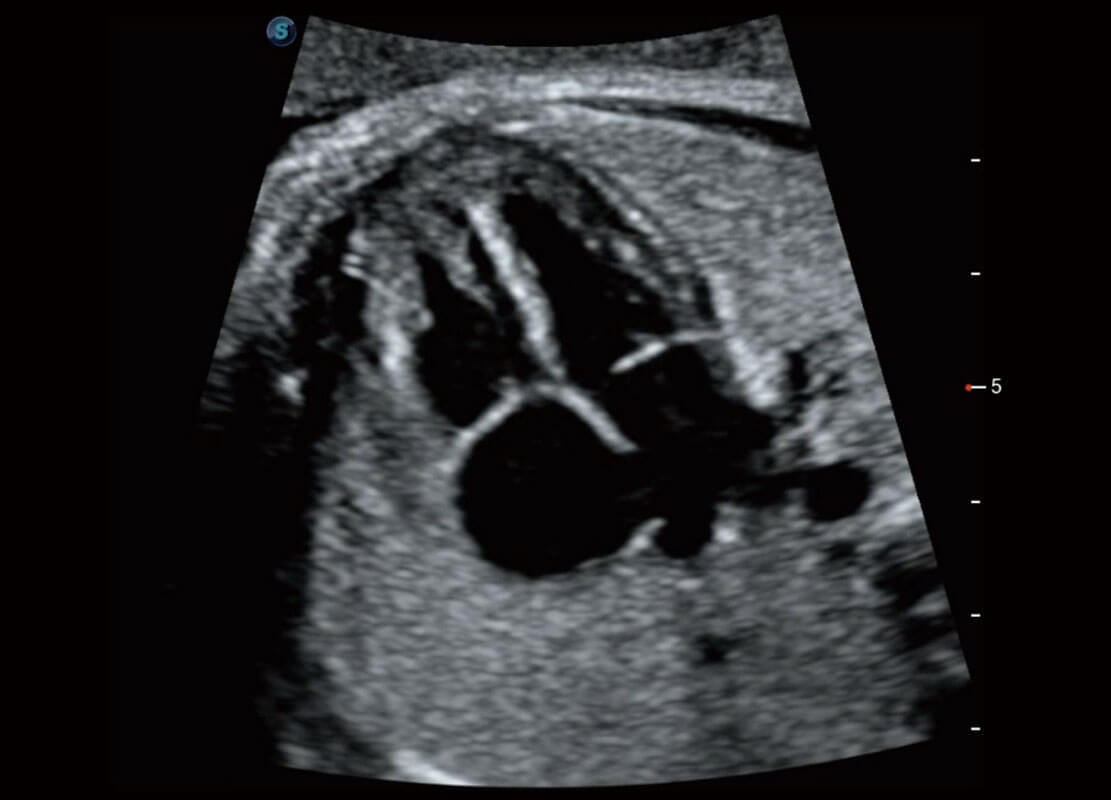

右室双出口

胎心容积成像